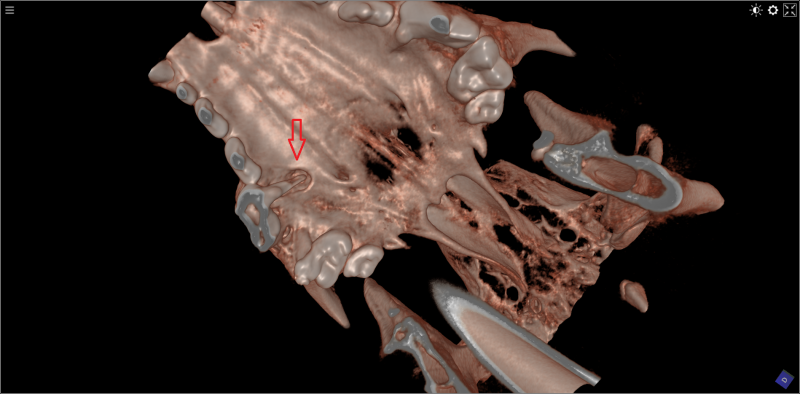

Kat van 11 jaar met bot tumor in de onderkaak